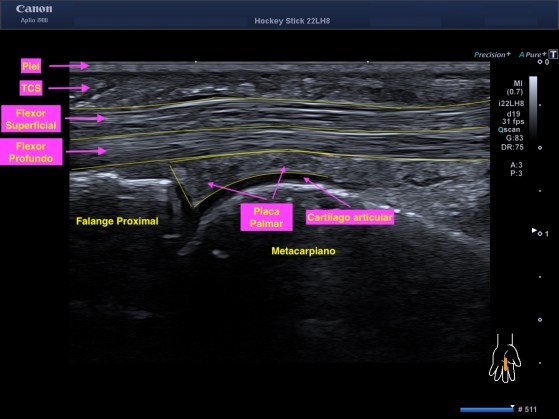

1. La Placa Palmar del dedo flexor de la mano.

Imagen en eje largo del tercer dedo en la cara palmar en su articulación metacarpofalángica.

De superficial a profundo:

Piel

TCS

Flexor Superficial

Flexor Profundo

Placa Palmar

Cartílago

Hueso

La Placa Palmar es una ecoestructura triangular que se inserta en la base de la falange proximal apuntándose hacia craneal y es de aspecto ecográfico homogéneo e hiperecogénico en su normalidad.